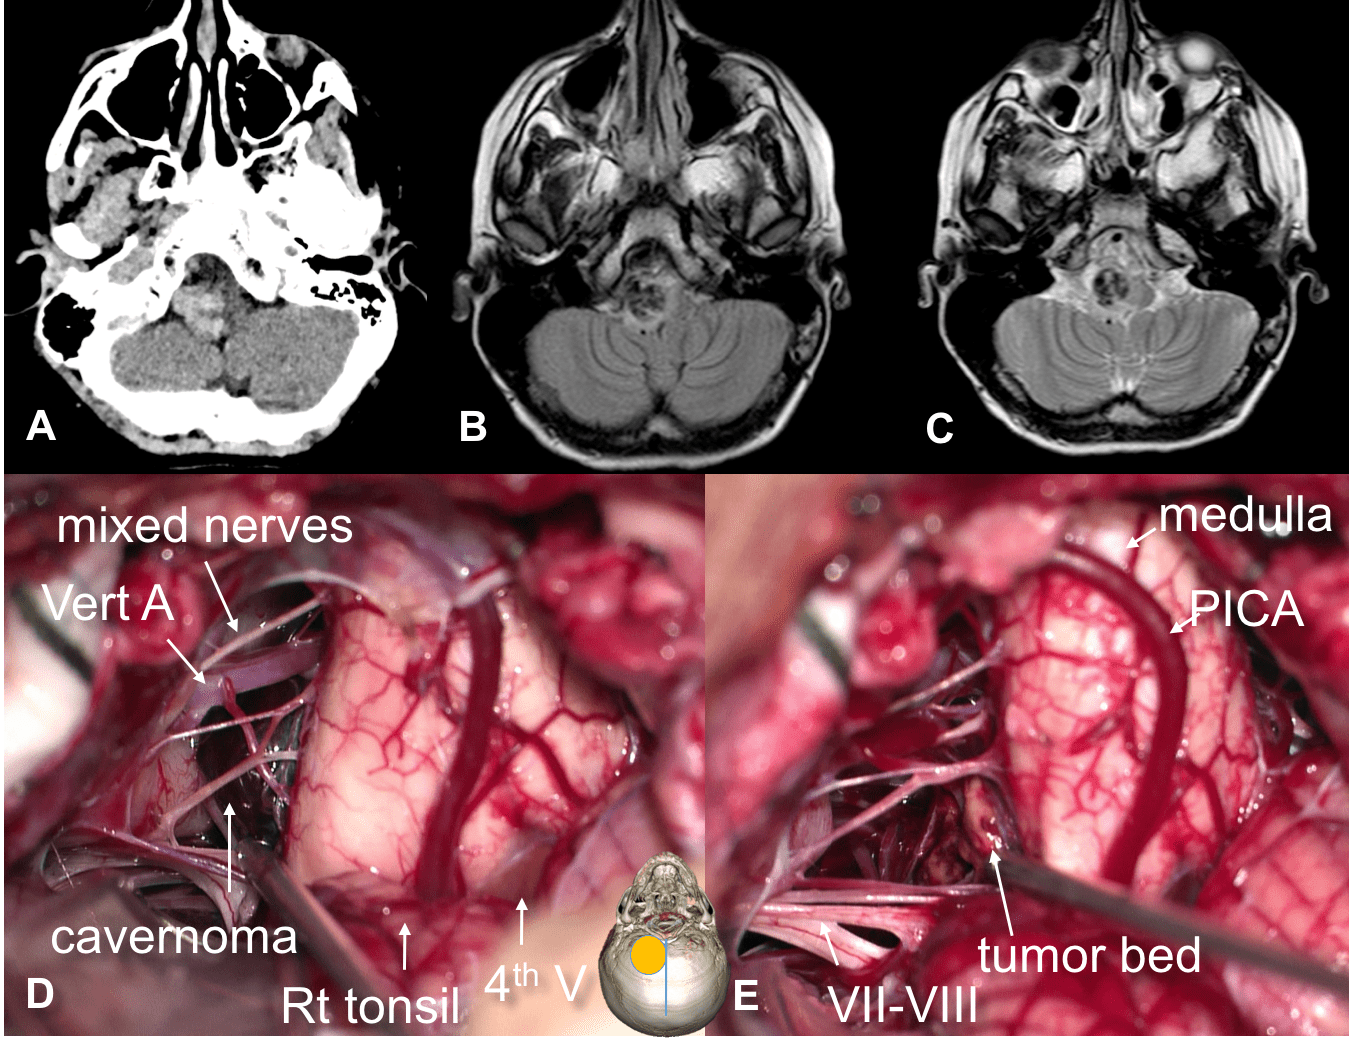

dans les cas d’une tumeur infiltrante (astrocytome pilocytique ou souvent gangliogliome), on doit se contenter de biopsies. en raison du caractère superficiel de ces tumeurs, de leur proximité des vaisseaux (PICA) et de la consistance ferme voire dure, il est souvent préférable de réaliser une biopsie à ciel ouvert que des biopsies stéréotaxiques.

l’abord postéro-latéral de la moelle allongée

les lésions intra-axiales qui affleurent au plan pial peuvent être abordées par une craniotomie occipitale médiane, avec dépose de l’arc de C1 et en élargissant la craniotomie du côté de la lésion. la dissection de la tonsille donne accès à la citerne latéro-bulbaire et l’angle ponto-cérébelleux.

cette voie d’abord nécessite une dissection soigneuse des nerfs mixtes et de l’artère vertébrale. l’abord bulbaire correspond au sillon pré-olivaire.

la section de la première digitation du ligament dentelé (repère de l’artère vertébrale) permet de gagner un peu de place latéralement mais n’améliore pas sensiblement l’axe de vision, qui reste tangentiel à la moelle allongée.

certaines lésions peuvent nécessiter un abord par le quatrième ventricule lorsqu’elle affleurent à la surface du plancher, comme les cavernomes.